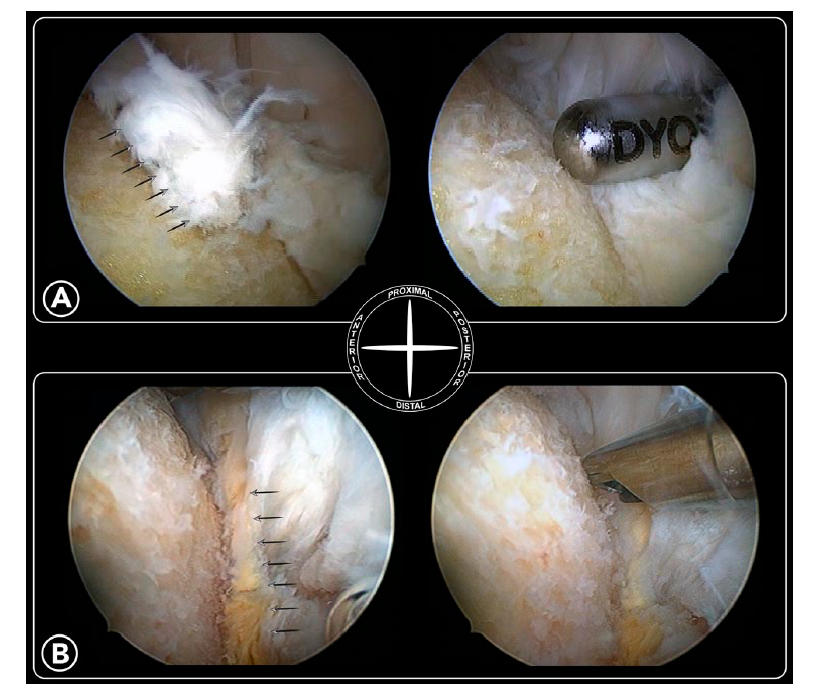

止点变性和钙化严重导致彻底清理后跟腱止点缺损超过50%时需要行跟腱止点重建。

50%-70%的跟腱止点切断,一枚锚钉固定:

跟腱完全从止点切开,用两枚单排锚钉固定:

双排锚钉固定相对于传统单排锚钉固定临床效果更好,满意度更高: